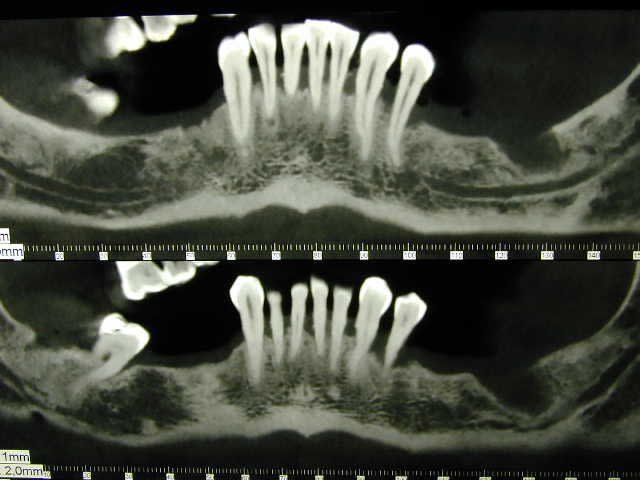

Voilà mon premier cas d'extraction-implantation immédiate et pose d'un bridge pilotis provisoire.

1)D'abord quels sont vos conseils et propositions? Vaut-il mieux démarrer dans ces conditions ou extraire, attendre la cicatrisation avec un complet, refaire un scan et implantation + provisoire?

2)Sur le scanner j'ai l'image du nerf dentaire et d'un nerf en dessous, de quoi s'agit-il ?

3) Le nerf incisif est proche des dents antérieures, que risque-t-on si on le sectionne lors du forage?